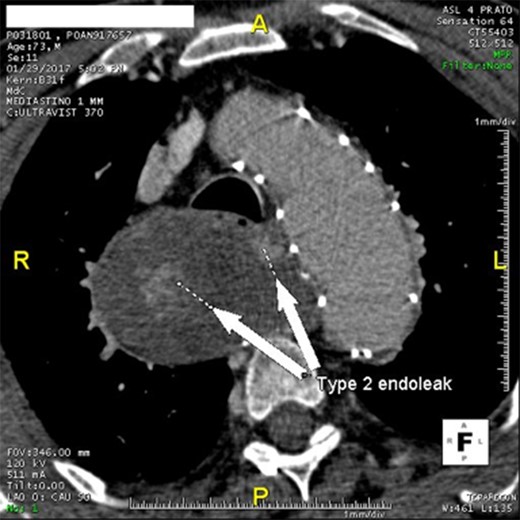

Twenty-two months after the procedure, the patient referred to our Unit due to the worsening of dysphagia. A new CT scan showed the enlargement of the aneurysmal sac (115 mm) due to the persistent Type II endoleak from bronchial arteries (Fig. 3). An endovascular embolization of the target vessels was not feasible due to the impossibility to cannulate the bronchial arteries without direct puncture. A preoperative esophageal endoscopy was performed to exclude the presence of esophageal–aneurysmal fistulas and an open repair with right thoracotomy and aneurysmorraphy of the AARSA was performed to occlude the bronchial side branches and to reduce the compression of the giant aneurysm on the esophagus (Fig. 4, 5). The postoperative course was uneventful and the patient was discharged on the 11th postoperative day.

Angio-CT scan at 22 months showing Type II endoleak with significant sac enlargement.